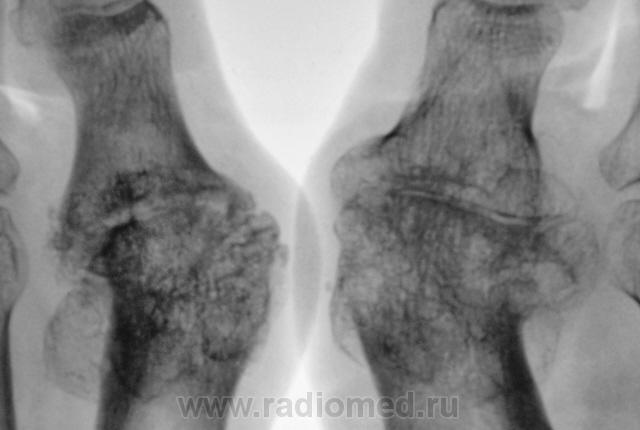

Пациентка направлена на рентгенографию стоп в прямой проекции с диагнохом - "Поперечное плоскостопие".

Произведена рентгенография обеих стоп в прямой проекции.

Думаю, что это дисхондроплазия - болезнь Олье.

Сильно сомневаюсь в болезни Олье - затронуты только суставные концы, диафизы интактны. Считаю - остеоартропатия, вероятнее всего - подагра

Классика подагры - наличие тофусов в параартикулярных мягких тканях... Механизм поражения скелета при подагре - атрофия от давления тофусами. А здесь - их совершенно не видно, мягкие ткани просто отодвинуты, но обьем то их - нормальный...

Согласен с артропатией, но подагра - сомнительно....

Поскольку артропатий великое множество....почему бы и не псориатическая...к примеру. Как там с анамнезом?